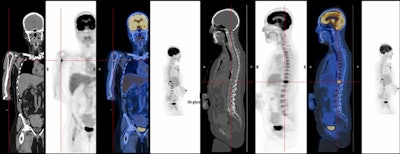

They added that it is also essential to know about the role of PET/CT in the follow-up of hematological diseases – particularly lymphoma, plasmacytoma, and multiple myeloma – and oncological pathologies, namely primary tumors and metastases.

Epidural space is the compartment most often affected by hematological neoplasm and primary bone tumors, and multiple myeloma is the most common primary bone neoplasm and the most frequent primary bone tumor that may lead to spinal cord compression. In these cases, MRI is the gold standard for diagnosis and PET/CT plays an important role in staging or follow-up, depending on the neoplasm of origin, the researchers stated.

In bone lesions, whole-body CT is a good initial examination for patients who have multiple myeloma. "If there are one or more 5-mm or larger lytic myeloma lesions, there is no need for the patient to undergo further investigation, with the exception of complication assessment, or treatment response evaluation, where the PET/CT plays an important role," they noted.

Therefore PET is valuable in soft tissue malignancies for staging, guiding biopsy, detecting recurrence, therapy response, and tumor grading, and it is a standard modality for staging both Hodgkin's disease and non-Hodgkin's lymphoma. In Hodgkin's disease, PET can be of value in any stage, but it is most useful in stage 1 and 2 disease, where a change in the stage will alter disease management, the researchers pointed out.

"PET is particularly useful in later stages of the disease, when response to chemotherapy is substantially lower than in early stages," they noted. "PET is also useful as a prognostic indicator after one or a few cycles or at mid treatment, during first line chemotherapy of Hodgkin's disease and non-Hodgkin's lymphoma; lack of response suggests that the treatment regimen should be changed."